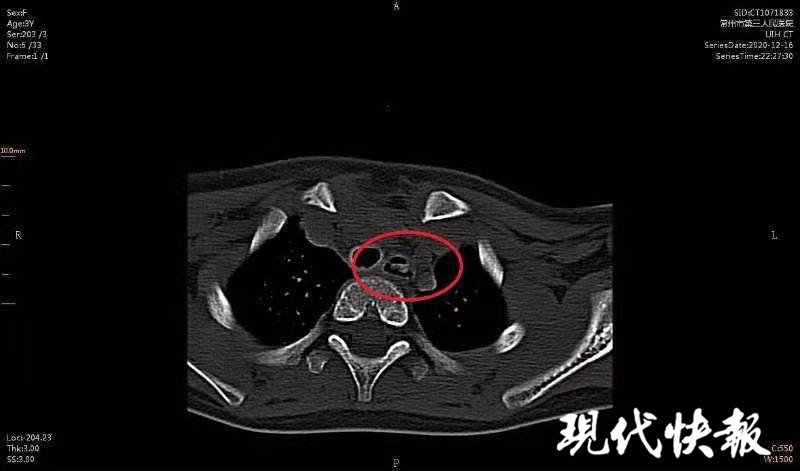

ct显示女童食道内有异物

图片尺寸800x471